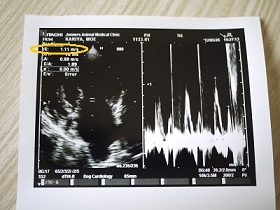

今日も測ってもらった波形(波計?)

血流のスピードを測定しているもので

前回のE波1.34m/s

今回は1.11m/s

同じ興奮時の測定でも 今日は下がってました。

1.5m/sに近いほど、肺水腫の可能性がある数値なので

下がって来ているのは、いい傾向です^^